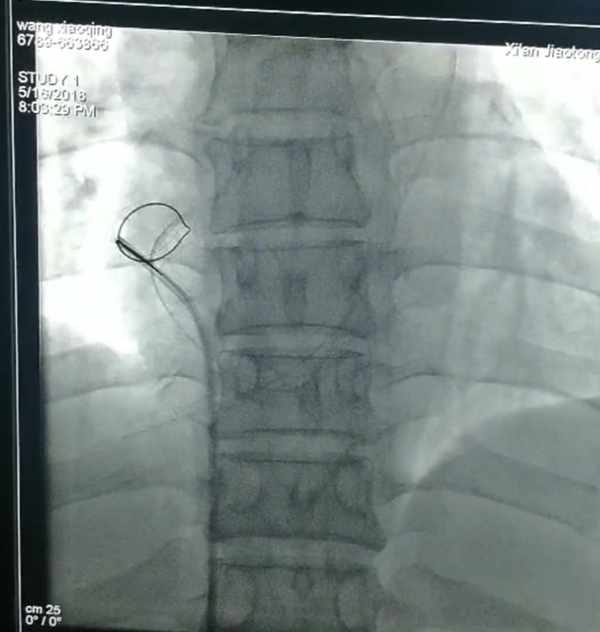

抓捕神器到位,看你哪里逃?

5月16日,该患者主管医师刘明教授、PICC置管专科护士张瑞丽老师与术者董新教授、李青医师商讨介入方案,心内科段宗明教授、朱参战教授、邓捷教授、张明娟教授、王蓉护士长也加入手术商讨中,心内妇产十余人观摩手术过程,简短的商讨后,患者被推入手术台。病骨支离的患者,四十多岁的人头发稀少看起来像老太太,全科人不禁感慨,大家心中默默为患者祈福。

消毒铺巾以最快速度完成,穿刺,确认部位,放入网篮导丝,寻找断裂残端,小心翼翼拉出断裂的导管,一整套手法,董新教授前后用了仅十余分钟!断裂体内的导管直径约1.5mm,长约41mm,管子抓出来那一刻全体欢呼雀跃,掌声一片。